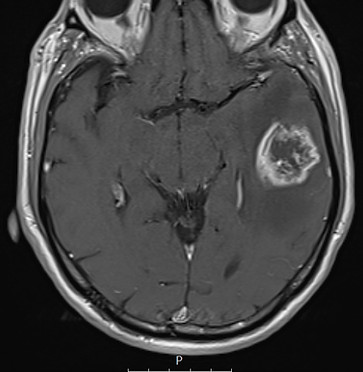

Glioblastoma - ļaundabīgs smadzeņu audzējs

Kreisā deniņa daivā redzams ļaundabīgs galvas smadzeņu audzējs pirms operācijas.

Kontrole pēc audzēja izdalīšanas no kreisās deniņa daivas - redzams pēcoperācijas dobums.